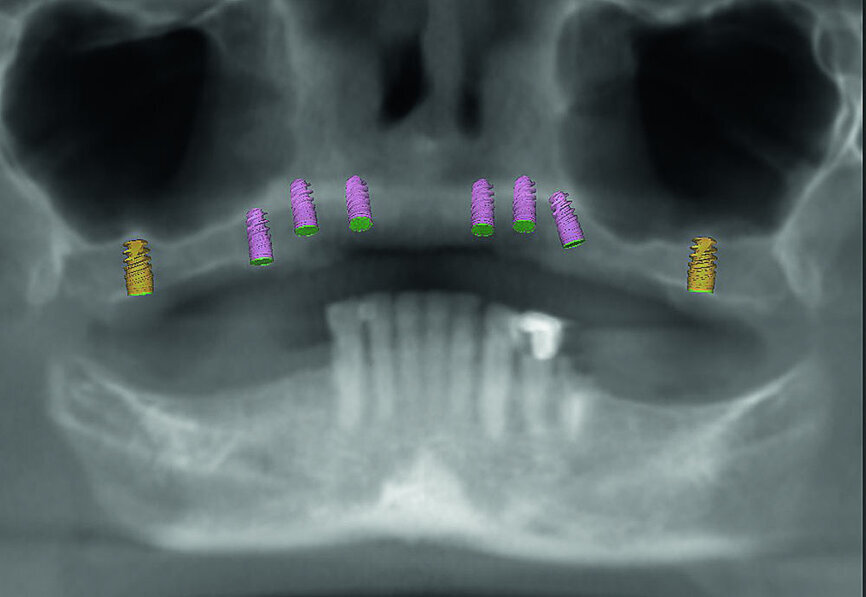

La patiente est revenue pour passer la visite des enregistrements. Au cours de celle-ci, des empreintes maxillaires et mandibulaires ont été prises afin de fabriquer des prothèses provisoires immédiates qui seraient mises en place lors de la visite prévue pour la chirurgie. Le scanner CS 8100 3D (Carestream Dental) a été utilisé pour acquérir des images CBCT, et obtenir ainsi les données nécessaires au plan de traitement virtuel. Les données 3D acquises grâce à la numérisation CBCT ont permis de déterminer les paramètres idéaux de longueur, de largeur et de positionnement des implants, aux endroits clés des arcades édentées de la patiente, soit les régions des premières molaires, premières prémolaires, canines et incisives centrales (Figs. 3–6). Des guides chirurgicaux à appui osseux maxillaire et mandibulaire ont été produits d’après le plan de traitement numérique conçu par 3D Diagnostix (Figs. 7 et 8).

Fig 5 Analyse dento-faciale du traitement implantaire proposé dans l’arcade maxillaire

Fig 6 Analyse dento-faciale du traitement implantaire proposé dans l’arcade mandibulaire